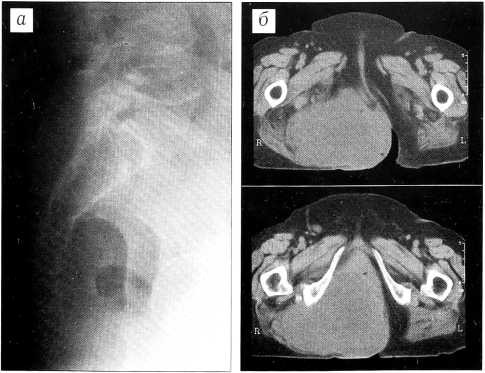

Больная М.,83 лет. В 1971 г. оперирована по поводу хордомы копчика, в 1993 г. выполнена повторная операция по поводу рецидива опухоли с проведением в послеоперационном периоде лучевой терапии. В 1997 г. госпитализирована в больницу № 62 с рецидивом опухоли. Опухоль достигала больших размеров (17x16 см), распространялась в левую ягодичную область и непосредственно предлежала к анальному отверстию. На рентгенограмме: крестец без явных костных деструктивных изменений до уровня S1-S3 (рис. 2, а). На компьютерной томограмме: по задней поверхности крестца определяется плотно прилежащее к нему мягкотканное образование протяженностью 9 см с четкими контурами (рис. 2, б). В ряде хирургических и онкологических учреждений больная была признана неоперабельной.

23.10.97 выполнена операция: опухоль иссечена в пределах здоровых тканей после предварительного формирования anus praeternaturalis. По ходу операции была повреждена прямая кишка, произведено ее ушивание. Гистологическое исследование опухоли: хордома. Послеоперационный период осложнился расхождением краев раны, которая зажила вторичным натяжением. Больная хорошо перенесла оперативное вмешательство, ходит, обслуживает себя. Физиологические отправления через противоестественный задний проход. Спустя 2,5 года признаков рецидива или отдаленных метастазов нет.

Рис. 2. Рентгенограмма (а) и компьютерная томограмма (б) больной М. Рецидив хордомы копчика.